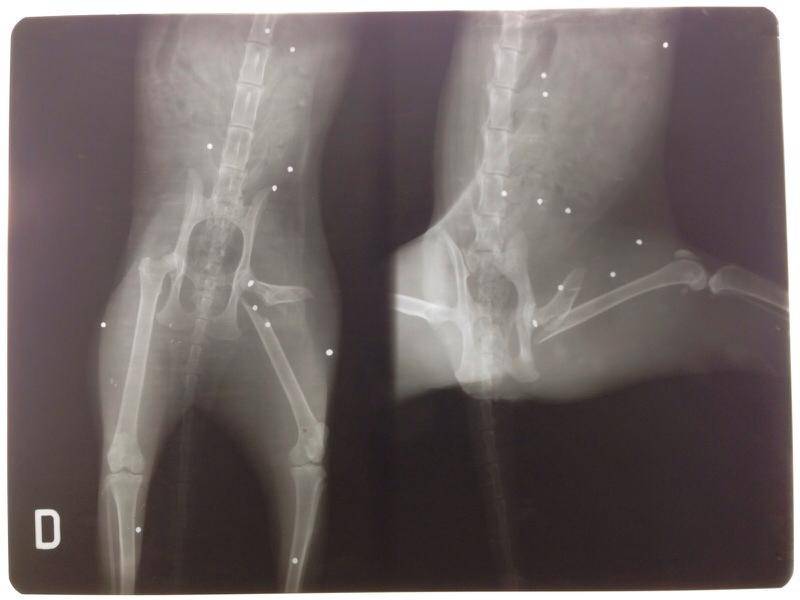

I medici hanno notato la presenza di decine di pallini di piombo presenti all’interno dell’animale da quando era probabilmente solo un cucciolo. I sanitari hanno chiesto subito informazioni a chi aveva consegnato loro il gatto, ma questi non sapevano nulla di quello del passato dell’animale. Qualcuno, forse quando era solo un cucciolo, si è divertito a sparare contro il povero felino con una pistola a pallini metallici. È stato escluso che si sia potuto trattare di un incidente data la quantità di pallini presenti. Uno dei veterinari che hanno in cura l’animale ha dichiarato: “I puntini sulla lastra e la cistite non sono collegati, ma è molto probabile che nei prossimi mesi o anni l’animale muoia per un avvelenamento da piombo”.